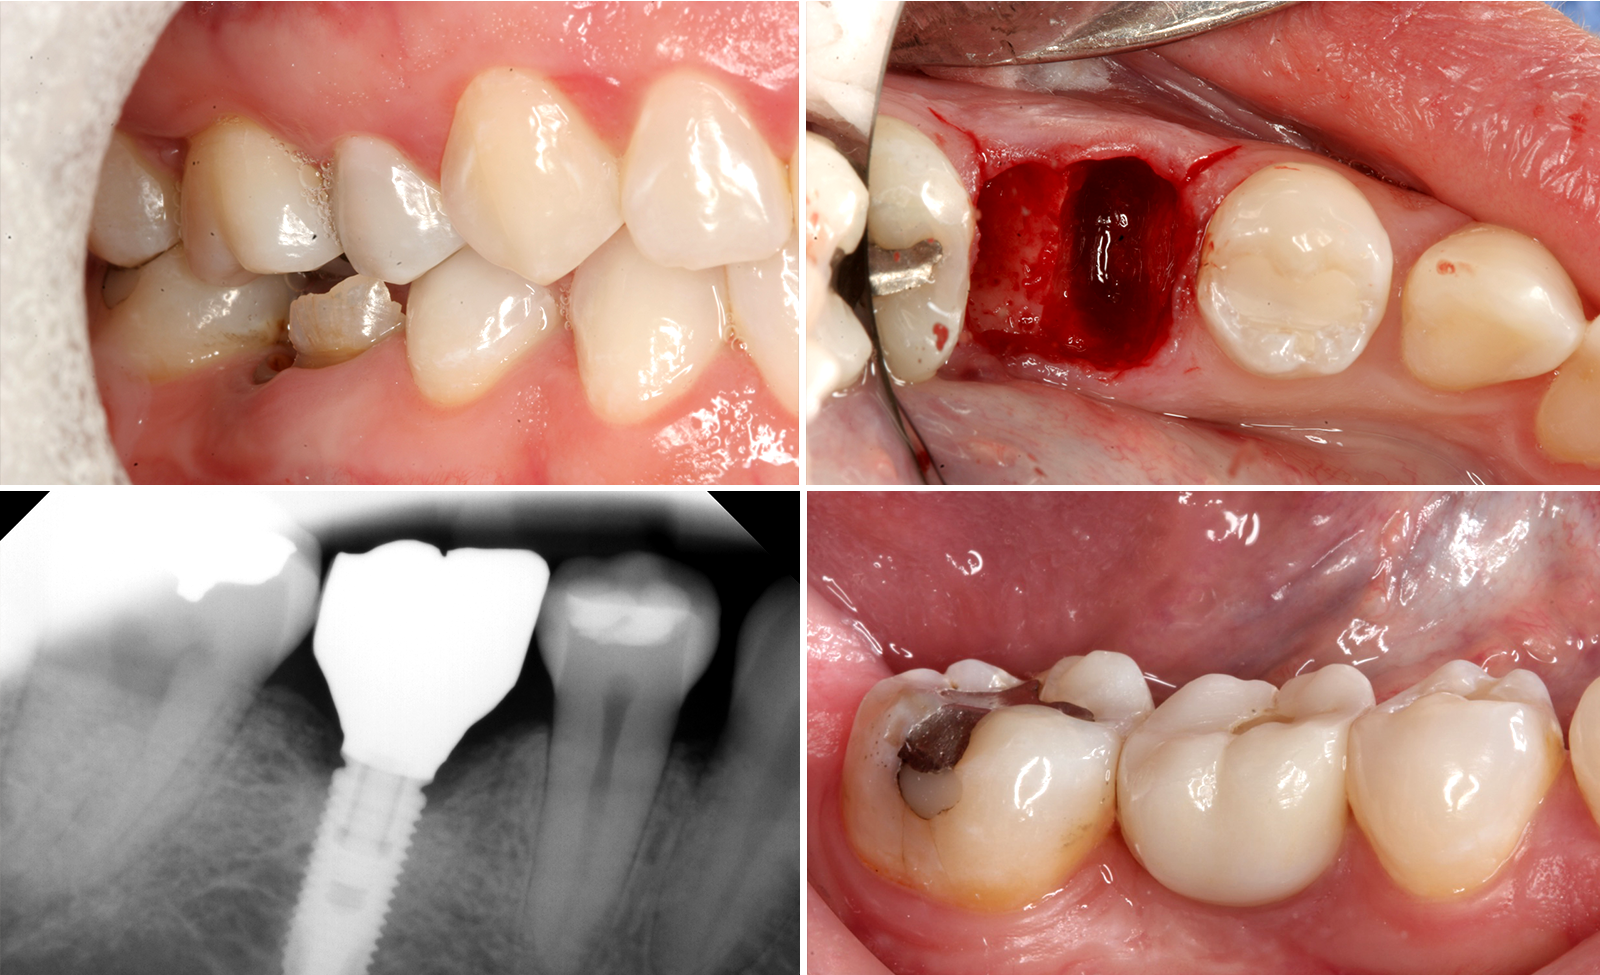

nena_clinical_4_photos